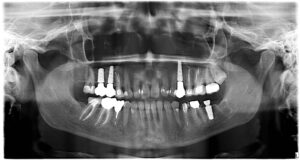

Tak tohle je mé intraorální já.

Pomalu zakončuju svoji dva a půl roku trvající stomatologickou misi. Řekla bych, že jsem v zubařském křesle strávila nějakou tu stovku hodin. Jen tenhle týden v pondělí pět a dnes dvě hodiny.

Sice bych za ty peníze měla asi notebook ze zlata, jenže genetika naší rodiny (co se zubů týče) je hodně neúprosná. A psát se dá přinejhorším i propiskou.